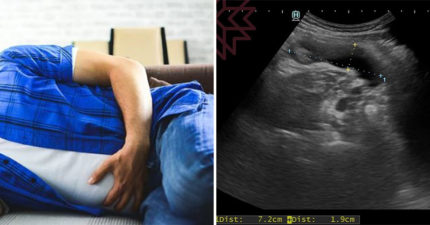

有腫瘤電腦斷層卻正常 醫檢查驚見「7cm大香腸」